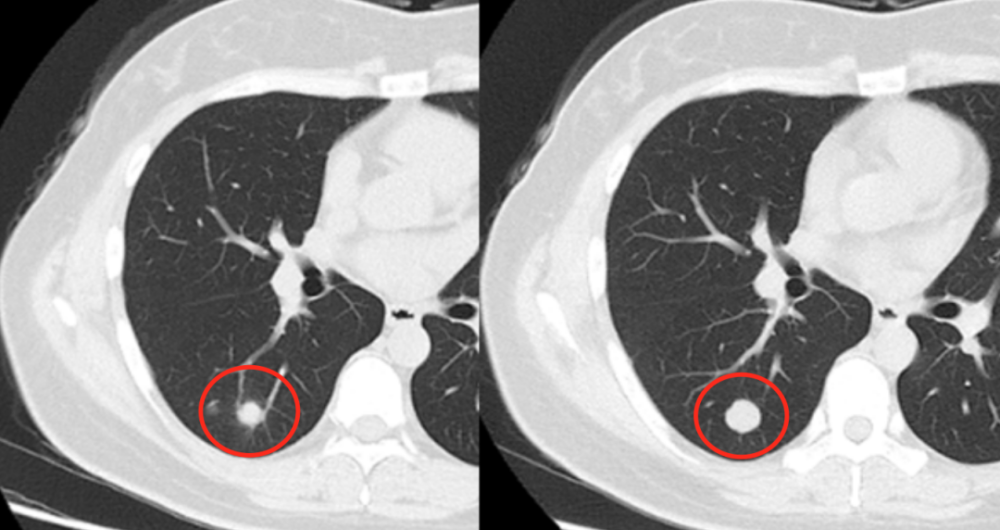

查出肺结节,哪3种需要动手术?医生用ct片举例说明

图片尺寸640x343